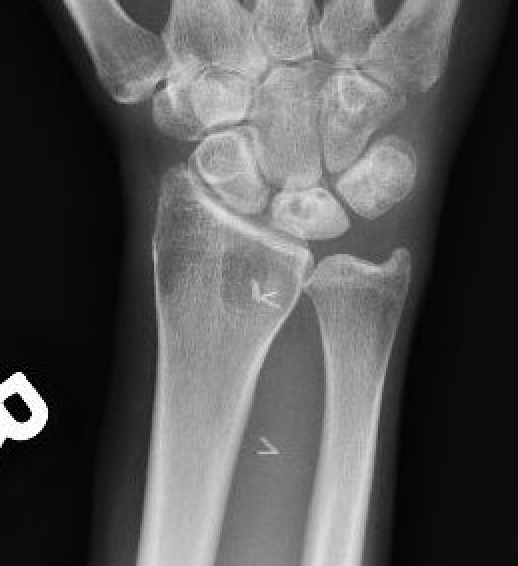

| Stage II | Stage IIIA |

|---|---|

| Sclerosis |

Collapse / fragmentation Normal carpal height |

![]() |